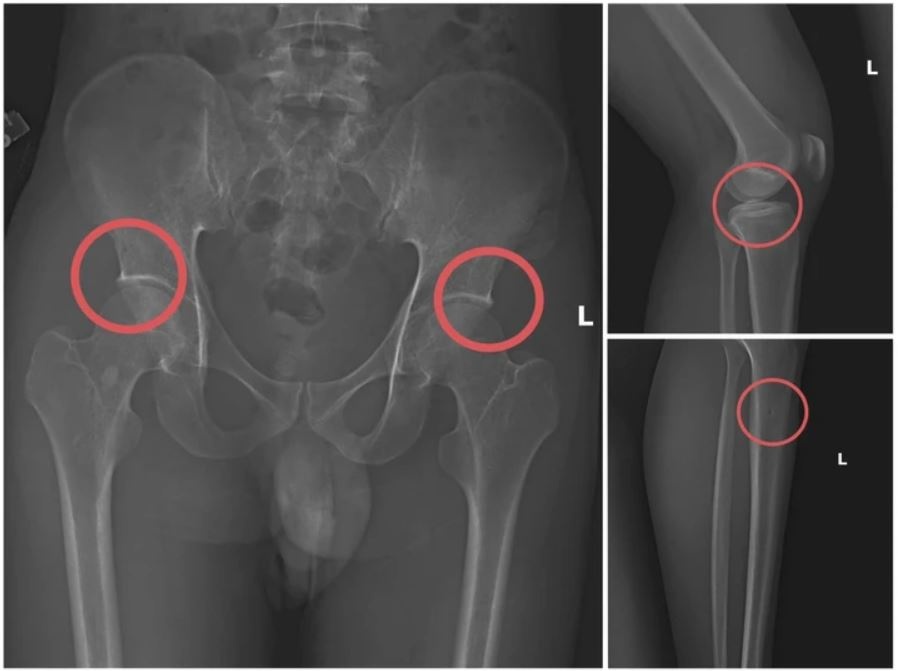

gay xuong lua bao hiem anh 2

Bản phim chụp XQ một số tổn thương xương do đối tượng tạo ra. Ảnh: Công an tỉnh Phú Thọ.

Đáng chú ý, Châu trực tiếp thực hiện hành vi tiêm thuốc mê, rồi dùng kim tiêm, búa... để tác động vào xương người mua bảo hiểm, tạo nên các vết nứt, vỡ xương tương tự tai nạn thật.

Lợi dụng thời gian dài công tác trong ngành Y tế và am hiểu sâu cấu tạo xương - khớp, cũng như cơ chế chi trả bảo hiểm đối với các thương tích gãy xương giá trị cao, Châu dựng lên một quy trình trục lợi bài bản, từ việc vận động mua bảo hiểm, tổ chức gây thương tích, đến hợp thức hóa hồ sơ bệnh án để chiếm đoạt tiền của các công ty bảo hiểm.